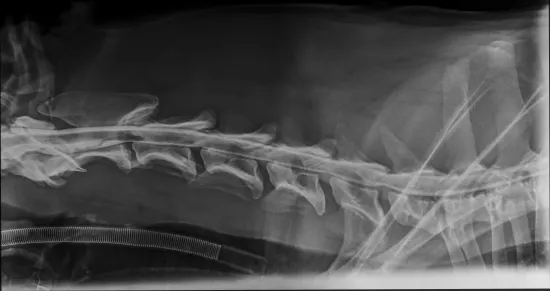

Niedawno trafił do nas starszy pies znaleziony przez pracowników stacji uzdatniania wody. Leżał skulony pod drzewem, cichy, bezbronny, jakby już pogodził się z losem. Kiedy pojechał po niego pracownik schroniska, szybko okazało się, że coś jest bardzo nie tak - pies ledwo się poruszał, z trudem wstawał, każdy krok sprawiał mu ból. Wezwany lekarz weterynarii stwierdził wstępnie zmiany zwyrodnieniowe, podał leki przeciwbólowe i wyraził zgodę na przewiezienie psa do schroniska. Niestety, gdy działanie leków zaczęło ustępować, Magik znów ledwo podnosił się z posłania. Zabraliśmy go do naszego weterynarza na dokładną diagnostykę. Dziś wiemy już więcej. Magik ma około 11 lat, a badania RTG wykazały poważne zmiany w kręgosłupie. Lekarz widzi wskazanie do operacji, ale zanim podejmiemy jakiekolwiek decyzje, konieczne jest specjalistyczne badanie - rezonans, które pokaże, co dokładnie dzieje się z rdzeniem kręgowym i czy operacja ma sens oraz jakie daje rokowania. Takie badanie możemy wykonać tylko w klinice we Wrocławiu. Koszt: 2500 zł. Od tego badania zależy dalszy los Magika. Jeśli okaże się, że można operować - zrobimy wszystko, aby dać mu szansę na życie bez bólu. Na operację uruchomimy osobną zbiórkę.